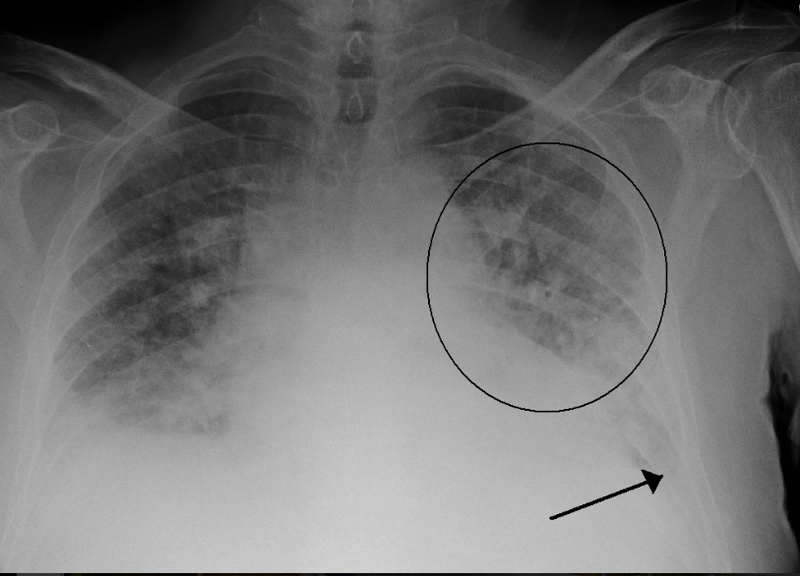

- X-ray ngực: Xem xét hình ảnh phổi để xác định sự sưng phù và tình trạng phổi.